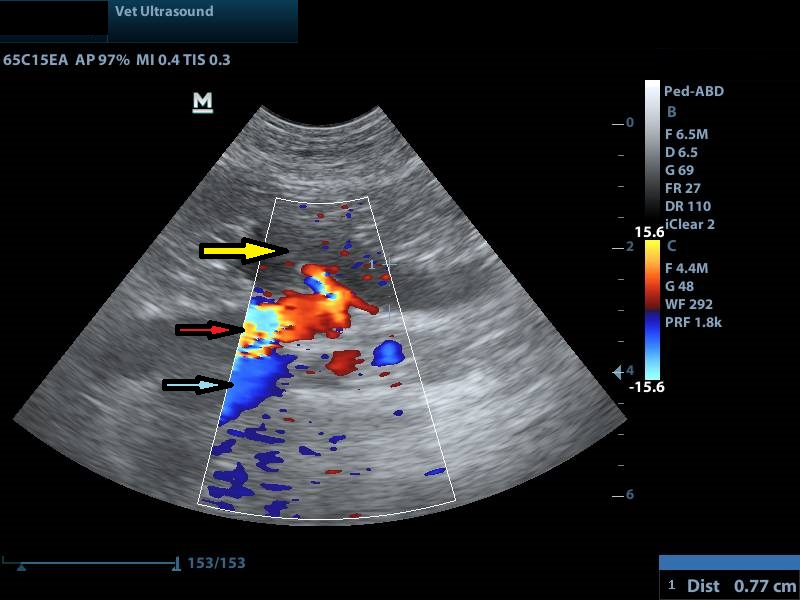

κίτρινο βέλος: διάταση του αριστερού ουρητήρα

κόκκινο βέλος: κοιλιακή αορτή

μπλε βέλος: οπίσθια κοίλη φλέβα